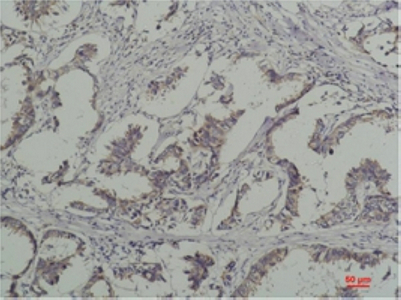

分类: 科研抗体货号: P20238别名: GYS1; GYS; Glycogen [starch] synthase; muscle应用: WB,IP,IHC,IF反应种属: Human,Mouse